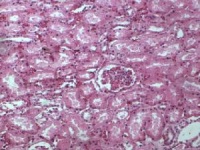

肾小管 shènxiǎoguǎn renal tubule 与肾小囊壁层相连的一条细长上皮性小管,具有重吸收(reabsorption)和排泌作用(secretion).肾小管按不同的形态结构,分布位置和功能分成三部分;近端小管,细段和远端小管。肾小管在肾髓质中。

近端小管可分为直部和曲部。其曲部又称近曲小管,位于皮质迷路内,于肾小体附近高度蟠曲。电镜下,其腔面有大量密集规则排列的微绒毛,即光镜下的刷状缘,细胞侧面除有连接复合体外,还有许多侧突,相邻细胞从侧突相互交错,故使细胞界限不清。细胞基底部有发达的质膜内褶,内褶之间的胞质内有大量纵行排列的基底纵纹,近曲小管的微绒毛。侧突和质膜内褶等结构与其功能密切相关。近端小管的功能主要是重吸收。

远端小管曲部也称远曲小管,位于皮质迷路内,远曲小管的长度比近曲小管短,因此在皮质迷路内的断面比近曲小管少,远曲小管在结构上基本与直部相似,但上皮细胞略大于直部,基底纵纹和质膜内褶不如直部发达,质膜内褶内的线粒体数量较少。

肾小管平均长约30~50mm,均由单层上皮构成,各段特点如下:

1.近曲小管 此管上连肾小囊腔是肾小管中最粗的一段,盘曲在所属肾小体周围。管壁由单层立方上皮细胞组成。管腔小而不规则,是肾小管重吸收功能的重要部分。细胞的游离面有刷毛缘。电子显微镜下可见刷毛缘是由微绒毛组成。这些结构都扩大了细胞表面积,有利于重吸收作用。

2.髓袢降支和升支 髓袢为一U字形小管,由三段组成:第一段为降支粗段;第二段为细段呈U形;第三段为升支粗段。第一段及第二段的降支部分又统称为降支,第二段的升支及第三段又统称为升支。它们分别由扁平和立方上皮构成。不同部位的肾单位髓袢的长度不同。皮质肾单位的髓袢较短,薄壁段很短或缺如。近髓肾单位的髓袢则较长,一直深入髓质可达锥体乳头。这类髓袢对尿的浓缩有特殊的功能。

3.远曲小管 较短。迂曲盘绕在所属肾小体附近,与近曲小管相邻。管壁由立方形上皮细胞组成,管腔大而规则。其末端与集合管相连。髓袢及远曲小管合称远端肾单位。

4.集合管 集合管是由皮质走向髓质锥体乳头孔的小管,沿途有许多肾单位的远曲小管与它相连,管径逐渐变粗,管壁逐渐变厚。管壁由立方或柱状上皮构成。过去认为集合管只有运输尿液的作用,现认为集合管亦有与远曲小管同样具有重吸收和分泌的功能。